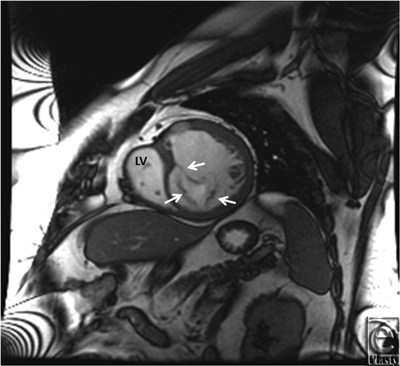

Initial 2D echocardiogram showed severe mitral valve regurgitation with a left ventricular ejection fraction of 35%. Furthermore, the valvular anatomy appeared peculiar; based on right ventricle (RV) and left ventricle morphology, CCTGA was suspected. A transesophageal echocardiography (TEE) was performed for further evaluation. It confirmed our diagnosis of CCTGA. Also, the (TEE) showed a hypertrophied RV and severe systemic AV (SAV) valve regurgitation (Figs 1 and 2). There was no evidence of an atrial septal defect, VSD, or patent ductus arteriosus. An MRI (magnetic resonance imaging) was performed to elucidate the anatomy. It affirmed the diagnosis of CCTGA with a trileaflet SAV that demonstrated severe regurgitation from the systemic ventricle (SV) to left atrium (Figs 3-6). Because of the patient's symptoms and severity of the regurgitation of the SAV, we decided to perform SAV replacement. Preoperative cardiac catheterization showed left dominant coronary circulation with left circumflex and a ramus intermedius originating from left cusp through separate ostia (Figs 7 and 8). Left anterior descending artery originated from proximal right coronary artery through a single ostium from right coronary cusp (Figs 8 and 9). No obstructive coronary heart disease was found and the patient proceeded to surgery.

![]() |

| Figure 7. Coronary angiogram showing origins of left circumflex (LCx) and ramus intermedius from different ostia on left coronary cusp. |